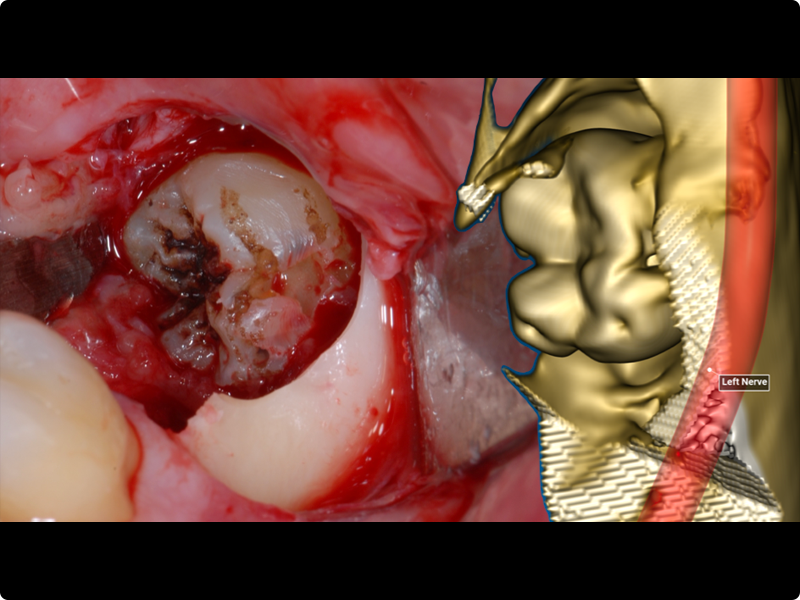

- Osteotomy.

- Odontotomy and rhizotomy.

- Dislocation and extraction.

Clinical cases of impacted third molar surgery and explanatory videos